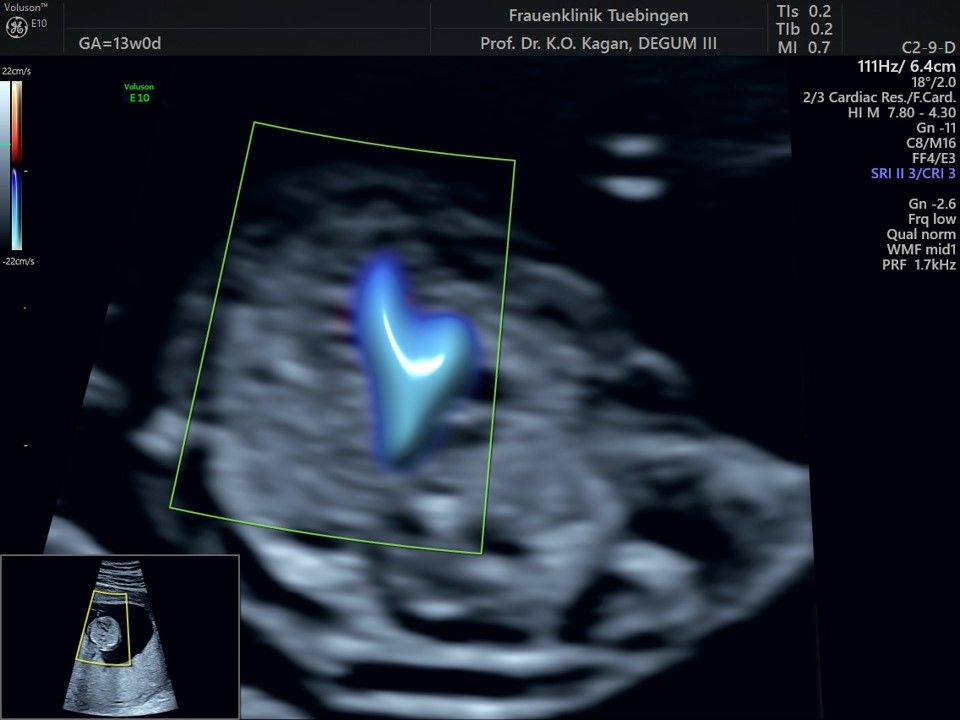

Herz

Das Ergebnis der Ultraschalluntersuchung ist wegweisend. Dabei wird der Fet vermessen, die Organe werden untersucht und die sonographischen Marker zur Risikoberechnung für Chromosomenstörungen werden beurteilt. Das sind: die Nackentransparenzdicke, Nasenbein sowie der Blutfluss in der rechten Herzhälfte und im Ductus venosus, einem Gefäß in der Leber des Feten.